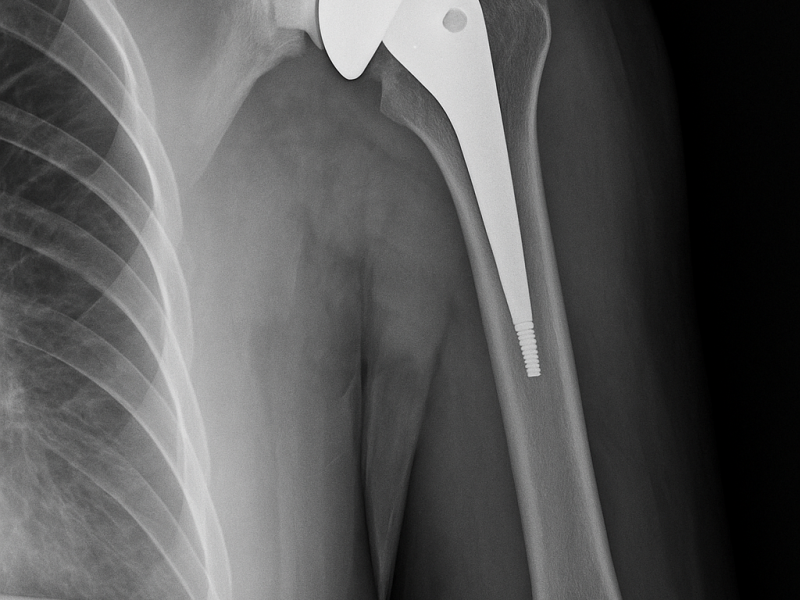

Il dolore alla spalla e la perdita di mobilità possono compromettere attività quotidiane semplici come vestirsi, sollevare il braccio o dormire senza fastidio. Quando l’articolazione è gravemente danneggiata, la protesi inversa di spalla rappresenta una soluzione efficace per recuperare funzione e ridurre il dolore.

Questa tecnica è particolarmente indicata nei pazienti con lesioni irreparabili della cuffia dei rotatori o con artrosi avanzata della spalla.

La protesi inversa modifica la biomeccanica naturale dell’articolazione, permettendo al muscolo deltoide di sostituire la funzione dei tendini danneggiati.